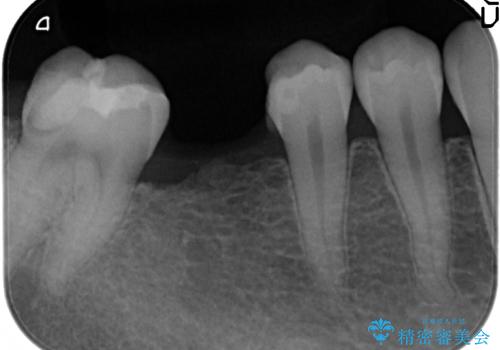

- 上下1本づつの歯を失い、噛めないことの改善を求めて来院されました。

保存可能な歯の虫歯・根管治療を行い、喪失した部分はインプラントを埋入、オールセラミックジルコニアクラウンを製作し審美的に仕上げていきます。

今回下顎の欠損部位はブリッジも検討されましたが、並行性の観点から最後方臼歯の神経を取るリスクを抑えるためインプラント治療を選択しました。